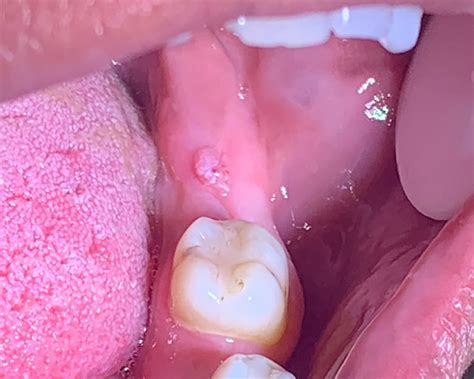

Discovering a small, wart-like growth inside your mouth can be an alarming experience, often triggering fears of serious disease. However, one of the most common benign lesions found in the oral cavity is the Oral Squamous Papilloma. This condition is essentially a localized proliferation of epithelial cells that results in a cauliflower-like or finger-like projection on the mucosal surface. Understanding what this lesion is, why it occurs, and when to seek medical advice is essential for maintaining oral health and peace of mind.

An Oral Squamous Papilloma is a benign, exophytic growth resulting from an infection caused by the Human Papillomavirus (HPV), most commonly types 6 and 11. Unlike malignant tumors, these papillomas are non-cancerous and do not have the potential to spread to other parts of the body (metastasize). They typically appear as solitary, painless, white-to-pink lesions with a roughened, pebbly surface.

Identifying an Oral Squamous Papilloma often involves observing its distinct morphology. Clinicians look for specific visual cues that differentiate this lesion from other oral pathologies like focal epithelial hyperplasia or squamous cell carcinoma. Because they are exophytic, they grow outward from the surface, often resembling a small cluster of grapes or a delicate cauliflower head.